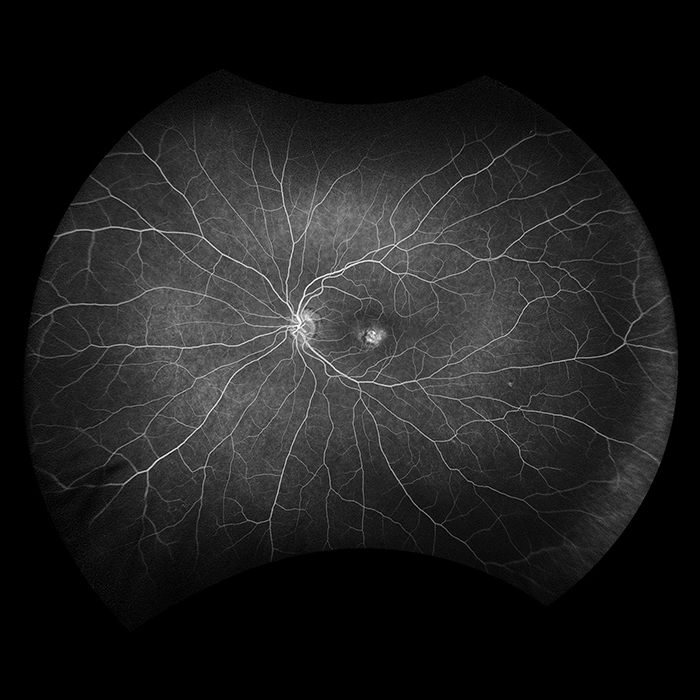

Silverstone RGB is redefining excellence in retinal imaging. It is the only device that captures true color, 200° optomap ultra-widefield images in a single shot, seamlessly integrated with guided swept-source OCT. For the first time, eye care professionals can access nine powerful imaging modalities in one system, each designed to image pathology anywhere in the retina.

optomap has been shown to enhance pathology detection, disease management, and to improve clinic flow. Now with nine retinal imaging modalities, including integrated, peripheral Swept Source OCT, Silverstone RGB facilitates examination of the retina from vitreous through the choroidal-scleral interface.

Silverstone RGB imaging modalities and image viewing options:

optomap Image Modalities

- color rgb

- color rg

- Sensory Retina

- Choroidal

- green af

- blue af

- fa

- icg

- SS-OCT